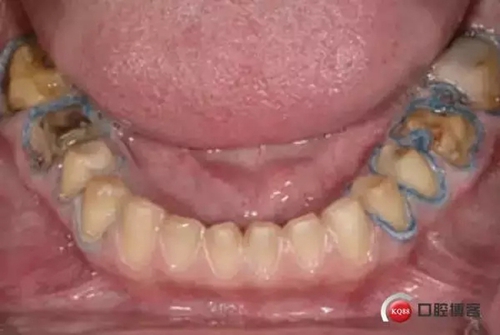

6. 輕柔的移除第二根排齦線, 第一根排齦線放置原處: 輕柔的干燥牙面,不要用力吹干。評(píng)估出血情況,水分控制情況和可見(jiàn)完整肩臺(tái)邊緣線。確定肩臺(tái)邊緣線是十分有必要的。

1498612936_946103.jpg